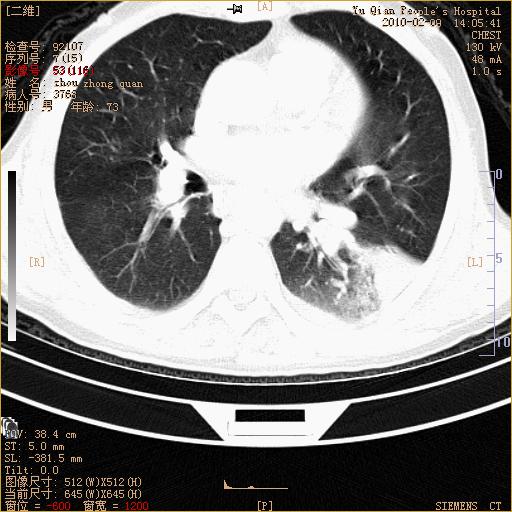

男性,73岁,咳嗽咳血数天,诊为肺ca伴左肺下叶后段阻塞性炎症、肺不张妥否?

右下肺有转移?

左下肺中央型肺癌伴结段形肺不张,左侧胸腔积液,纵隔内见部分增大淋巴结(反应性增生或转移)

左下基底干支气管明显变窄。

左肺下叶基底段支气管狭窄,左肺门增大,左肺下叶团片状病灶。中心型肺癌伴柱塞性炎症可能大,建议支气管镜检查。

左下肺中央型肺癌伴节段性肺不张,左侧胸腔积液,纵隔内见肿大淋巴结

左下基底段支气管变窄。建议进一步纤支镜检查。

1、左肺下叶后基地段肺癌伴阻塞性炎症,左下肺门淋巴结转移。2、左侧胸腔积液。